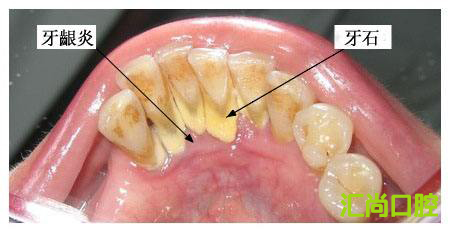

首先,我們經(jīng)常見到牙縫里面的紅色物質,這種物質被稱作牙菌斑,牙菌斑是粘附在牙齒表面的,不易被沖走,這就給更多的細菌提供肥沃的土壤,而且一般會在兩小時左右迅速增厚,所以我們應當在12小時左右清除牙菌斑。

然后,如果清除不及時,細菌就會大量繁殖,如果再不注意口腔衛(wèi)生,牙菌斑和食物殘渣會在唾液的浸泡下經(jīng)過24小時被唾液中的成分鈣化,這就形成了初期的牙結石。隨著時間的推移,牙結石會繼續(xù)沉積,越積越多,越積越硬,到后期刷牙是去不掉的,只能通過洗牙去解決。

第二:導致牙齦疾病。牙結石如果長期不處理,會引起牙齦組織的水腫、充血、糜爛等情況,如果繼續(xù)發(fā)展,可造成牙周組織溢膿,甚至牙齒松動。如果是孩子,一定要防止牙結石的形成,否則成年后就可能成為牙周病患者的一員。

第三:導致牙齒松動。牙結石從牙冠逐漸向下蔓延,牙結石每進步一些,牙槽骨就萎縮一些。久而久之,牙齒就逐漸松動,這時牙結石便見縫插針,逐漸蔓延到牙根部位,嚴重的會導致牙齒脫落。